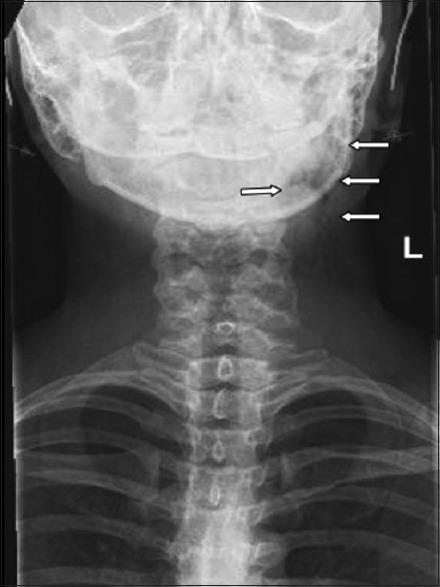

Cervicofacial and mediastinal emphysema due to a dental procedure.

Dental procedures, though commonplace and usually very safe, are not without complications. We report on a case of extensive cervicofacial and mediastinal emphysema after a routine dental procedure, initially masquerading as an allergic reaction in an otherwise young and healthy woman. A review of the relevant literature on this clinical entity is presented, which serves to underscore the need for awareness by the treating clinician of this condition and its potential sequela.

牙科手术虽然常见且通常非常安全,但并非没有并发症。我们报告了一例常规牙科手术后发生广泛颈面部和纵隔气肿的病例,该病例最初在一名年轻健康的女性身上伪装成过敏反应。本文对有关该临床实体的相关文献进行了综述,强调了治疗临床医生认识这种情况及其潜在后果的必要性。